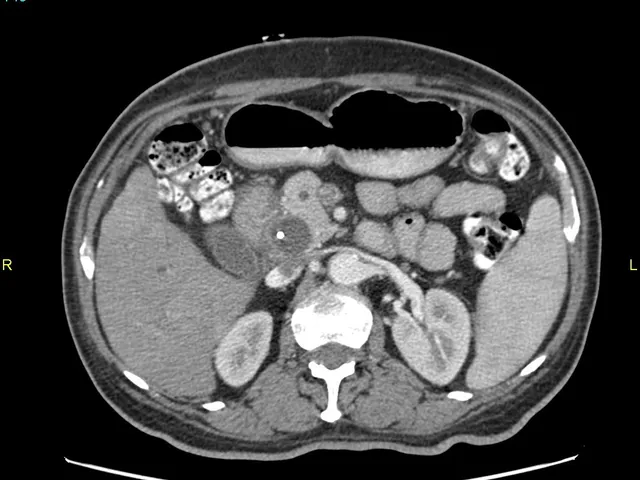

Pancreatitis

The aim of this module is to describe the main imaging findings in acute and chronic pancreatitis.

CT and MR imaging scans will be used for teaching purposes to describe the most typical imaging findings and most frequent complications in acute and chronic pancreatitis.

- To describe the main imaging features of oedematous acute pancreatitis

- To describe the main imaging features of necrotic acute pancreatitis

- To describe the main complications of acute pancreatitis